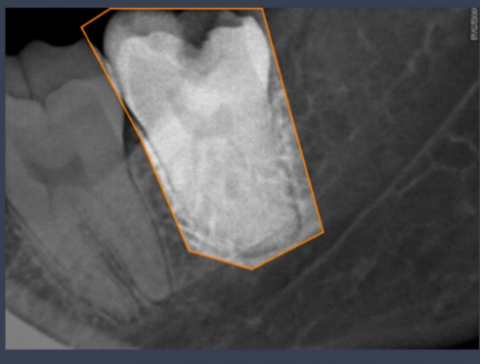

Figure 3. Labeled data image

In the labeling process, the diseases in each image are identified and labeled, as shown in Figure 3. This process aims to ensure the correct classification of the data to be used in the training of the model.